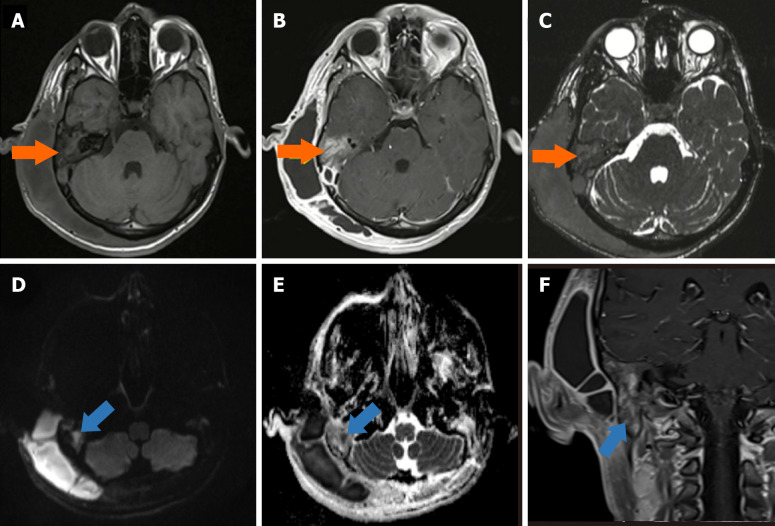

慢性中耳炎(COM)是一种影响中耳和乳突腔的长期炎症,通常导致进行性结构损伤和功能缺陷。放射成像是诊断疾病、评估其严重程度和识别可能的并发症的基础。文献显示颅外、颅内合并症患病率为0.69% ~ 5%,颅内合并症死亡率为26%。虽然磁共振成像在区分软组织异常和检测颅内延伸(如脑膜炎、脑脓肿和乙状窦血栓形成)方面特别有用,但高分辨率计算机断层扫描仍然是评估骨侵蚀、胆脂瘤和乳突受累的首选方式。关键并发症,如听骨链破坏、面神经损伤和迷路瘘管可以通过先进的成像方式精确识别,允许及时有效的手术干预。这篇小型综述强调了放射学在诊断和治疗COM中的重要作用,强调了有助于早期发现和指导治疗决策的关键影像学发现。放射科医生、耳鼻喉科医生和传染病专家之间的合作方法对于改善受影响患者的临床结果至关重要。

Chronic otitis media (COM) is a long-standing inflammatory condition affecting the middle ear and mastoid cavity, often resulting in progressive structural damage and functional deficits. Radiological imaging is fundamental in diagnosing the disease, assessing its severity, and identifying possible complications. The literature indicates that the prevalence rates of extracranial and intracranial complications range from 0.69% to 5%, while the mortality rate for intracranial complications is 26%. While magnetic resonance imaging is particularly useful in distinguishing soft tissue abnormalities and detecting intracranial extensions like meningitis, brain abscess, and sigmoid sinus thrombosis, high-resolution computed tomography remains the preferred modality for evaluating bony erosion, cholesteatoma, and mastoid involvement. Key complications such as ossicular chain destruction, facial nerve damage, and labyrinthine fistulae can be precisely identified using advanced imaging modalities, allowing for timely and effective surgical intervention. This minireview underscores the essential role of radiology in both diagnosing and managing COM, highlighting critical imaging findings that facilitate early detection and inform treatment decisions. A collaborative approach among radiologists, otolaryngologists, and infectious disease specialists is crucial for improving clinical outcomes in affected patients.